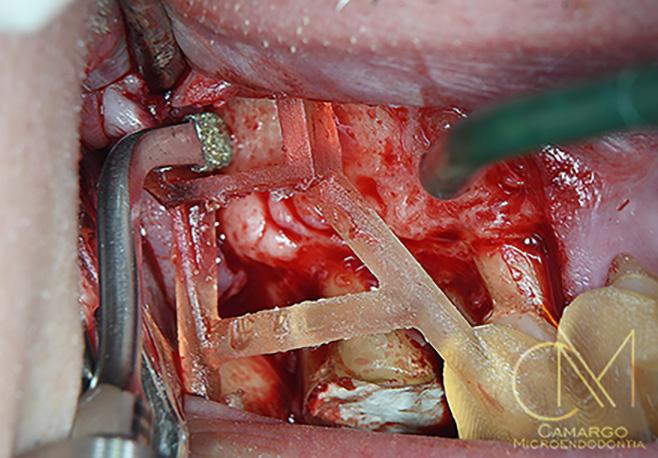

| A Tomografía computarizada de haz cónico (CBCT) coronal o sagital que muestra la proximidad de la lesión periapical y el seno maxilar. | B Oclusión correcta antes del tratamiento. | C Plantilla quirúrgica 3D para guiar el acceso. | D Osteotomía con el Piezotome Cube (Acteon, EE. UU.) usando la punta SL1 después de elevar el colgajo. | D Osteotomía con el Piezotome Cube (Acteon, EE. UU.) usando la punta SL2 | F Preparación retrógrada sobre la raíz mesiovestibular con una punta Berutti (EMS, Suiza) e irrigación salina. | G Biocemento Bio C Repair (Angelus, Brasil) aplicado en el conducto mesiovestibular. | H Fotografía con el microespejo de 3 mm para comprobar la obturación retrógrada en la raíz distovestibular del segundo molar derecho superior. | I Geistlich Bio-Oss® Small 0,5 g. (Geistlich Pharma AG, Suiza) en el sitio quirúrgico. | J Cavidad quirúrgica rellenada con Geistlich Bio-Oss® Small. | K Membrana Geistlich Bio-Gide® 25 × 25 mm usada para cubrir el injerto. | L Radiografía final después de la cirugía.

17 A B C D E F J K L H I G

FIG. 1: Microcirugía periapical regenerativa para tratar la periodontitis apical alrededor de las raíces mesiovestibular y distovestibular del diente

Fotografías: Jose Mauricio Paradella de Camargo

La microcirugía periapical regenerativa incluye los siguientes pasos (figura 1):

1. Aumento mejorado para una resección mínima de la raíz;

2. Preparación ultrasónica del ápice de la raíz;

3. Obturación retrógrada con un mate rial biocerámico para la reparación de la raíz; y

4. Regeneración tisular guiada en el lu gar del defecto óseo.